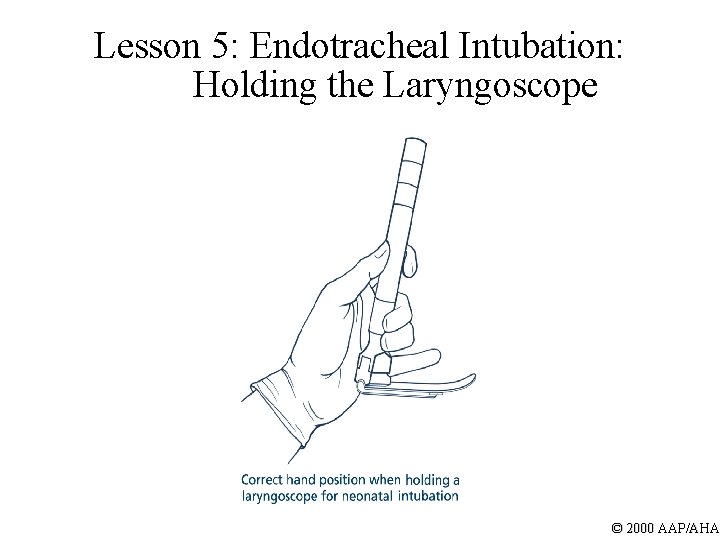

Lesson 5: Endotracheal Intubation: Holding the Laryngoscope © 2000 AAP/AHA